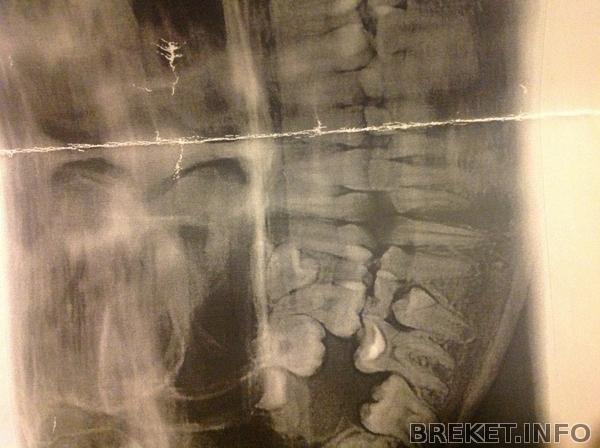

Я начала волноваться!тут снимки. Справа(слева для вас) зуб который находится совсем не в том положении.Мне начали рассказывать (на сайте) об операциях во многих таких случаях как там что то вырезают.нет на операцию я не пойду!Может все там нормально.Сейчас в этом промежутке разьединяются зубы,думаю то что это этот зуб будет вставать на место.Вух очень надеюсь

image.jpg